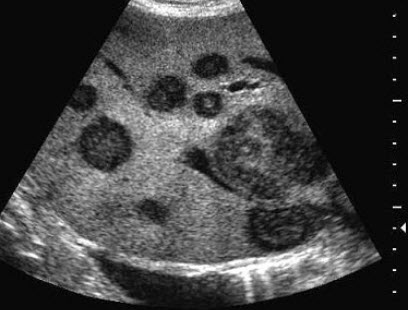

如图所示,双肾结构清晰,左肾体积小,该病例最可能诊断是( )

A:肾发育不良

B:肾萎缩

C:慢性肾炎

D:肾结核

E:慢性肾衰